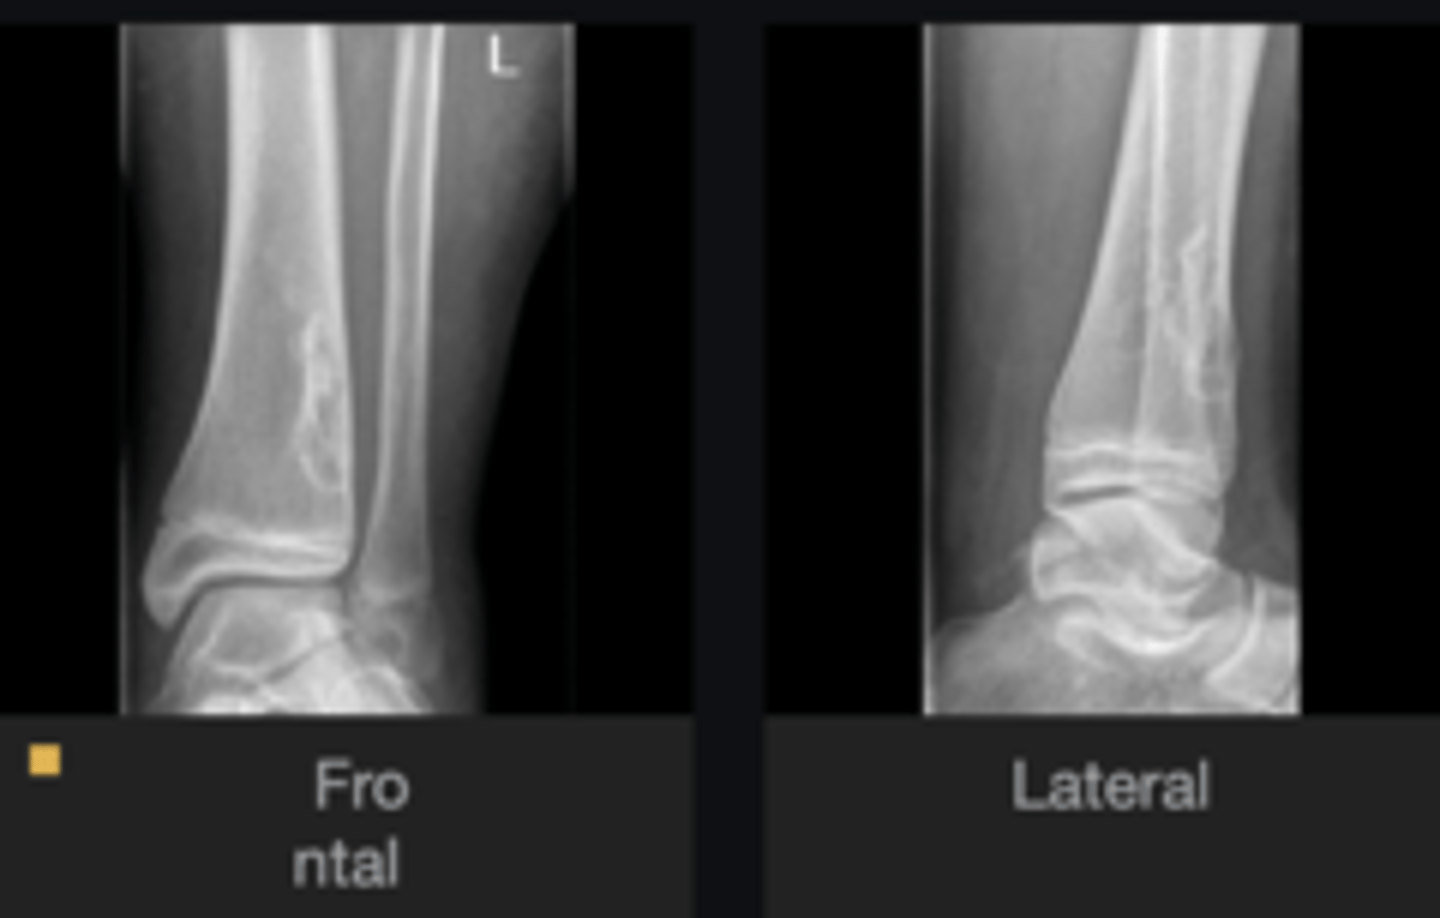

- Body of calcaneus

- Geographic

- Lucent

- Central target sequestrum

Describe the lesion

<p>Describe the lesion</p>

Intraosseous lipoma

Most likely diagnosis?

<p>Most likely diagnosis?</p>

Refer to orthopedist or specialist

Next step?

<p>Next step?</p>

Heel spur

What is going on with the posteroinferior calcaneus?

<p>What is going on with the posteroinferior calcaneus?</p>